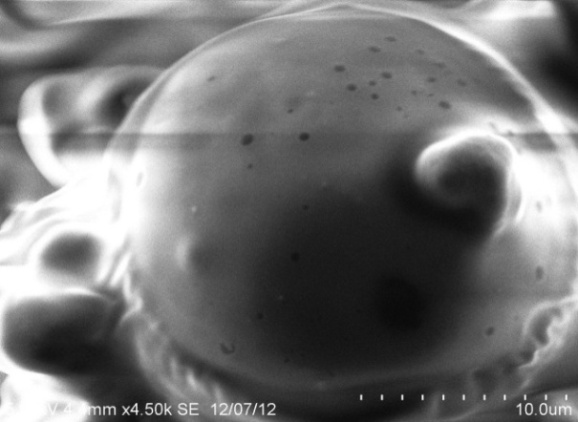

Morphology of microspheres

The magnetic chitosan microspheres were spherical and aggregated. As showed in Fig. 1 A and B, magnetic microspheres appeared black in colour and confirmed the encapsulation of magnetite. SEM pictures (Fig. 1. C and D) confirmed spherical nature and aggregation of microspheres. The surface of magnetic microspheres was rough (Fig. 1E) in contrast non-magnetic microspheres were smooth (Fig. 1F). The presence of magnetite in the microsphere resulted in an uneven and rough surface.

Fig. 1: Photomicrographs (40 x magnifications, A, B) and SEM pictures of chitosan microspheres loaded with magnetite and 5 FU(C, D). Surface morphology of microspheres with (E) and without magnetite (F)